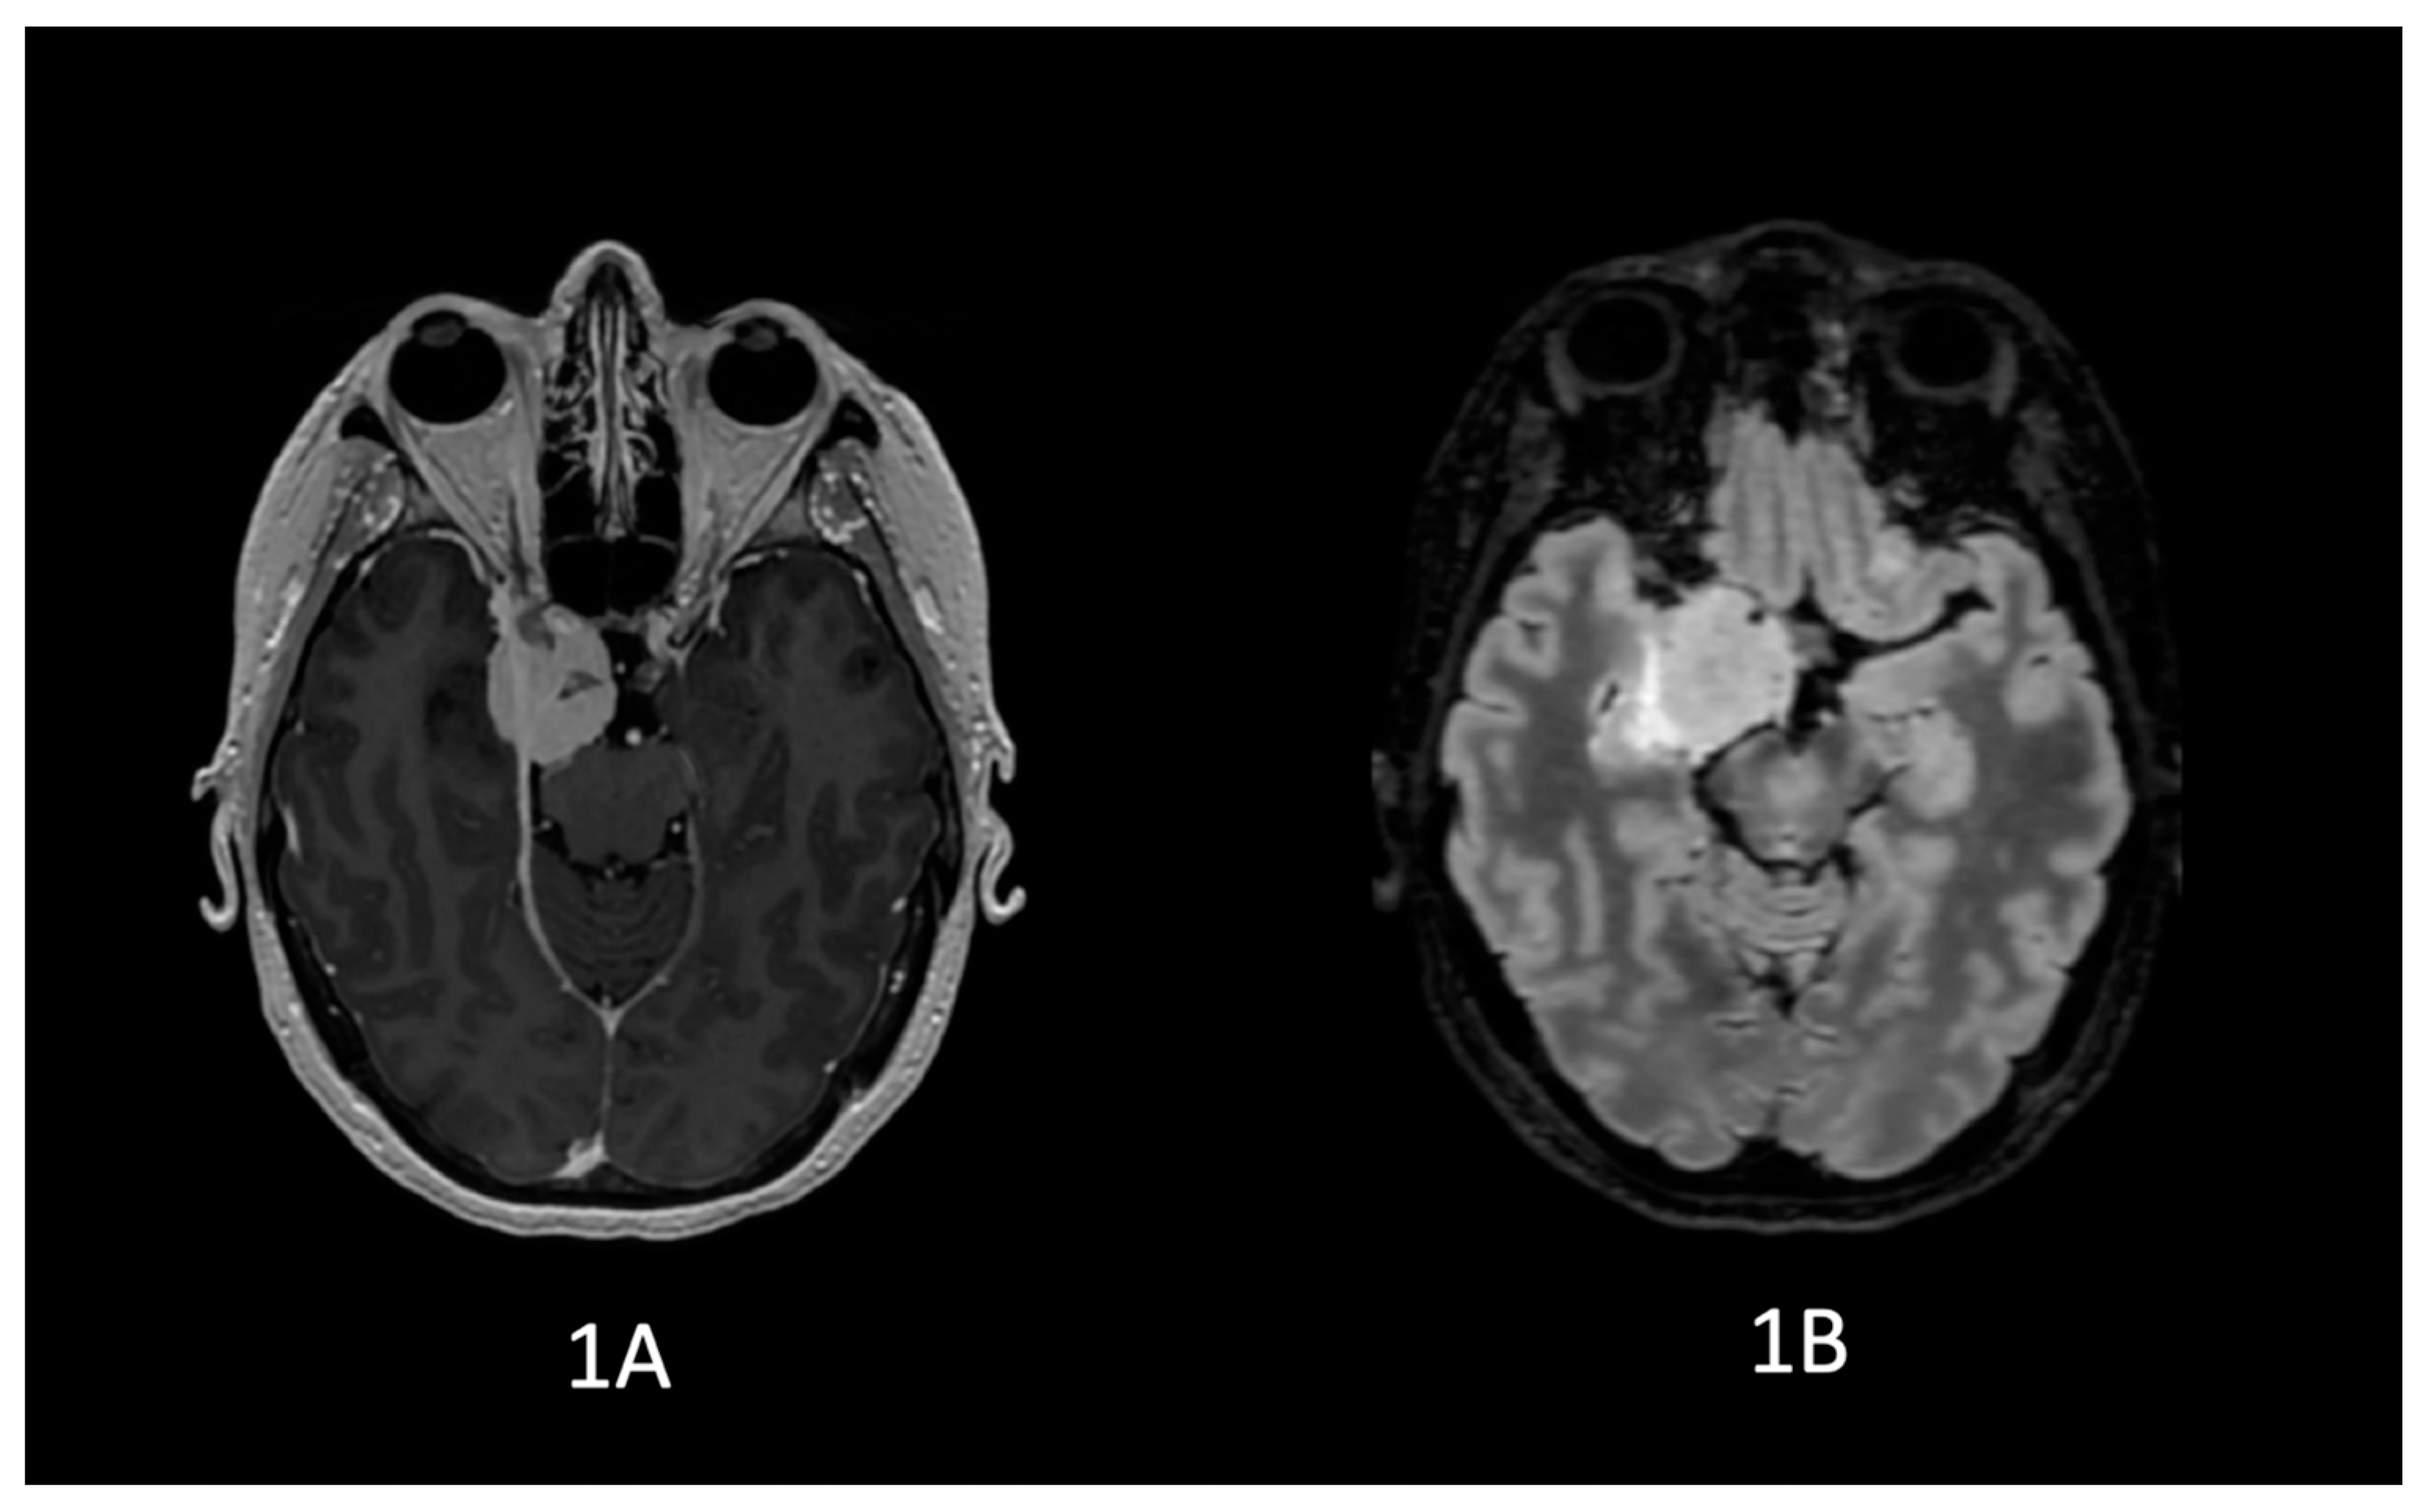

5.3. Complementary Studies

5.3.2. Diffusion Tensor Imaging (DTI) Tractography

- The paroxysmal episodes of divine conviction were directly related to epileptic activity and alteration of the uncinate fasciculus.

- The correlation with alteration of the right uncinate fasciculus supports the hypothesis that this white matter tract may act as a key modulator in the propagation of epileptic activity toward frontal regions involved in meaning attribution.